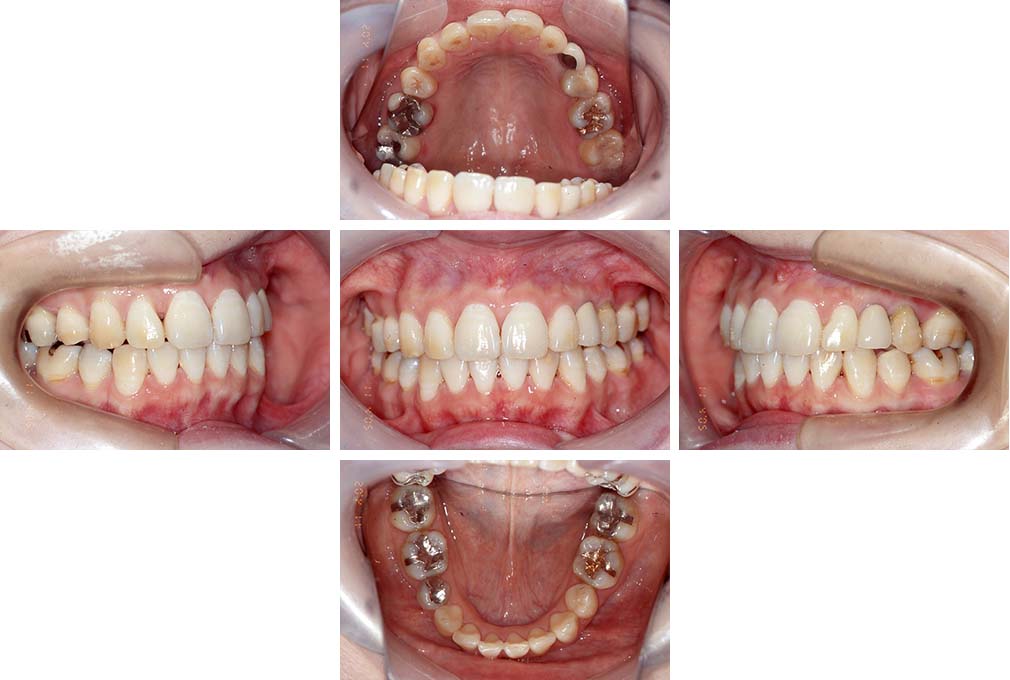

CASE:04

アングルⅢ級傾向を持つ叢生

初診時年齢 22歳

性別 女性

治療費の目安 105万円程度(治療開始時)

上顎右側犬歯が唇側に転位していることを主訴に県内歯科医院から紹介来院された。骨格的にはⅢ級傾向で上顎右側犬歯が唇側転位となり、側切歯が口蓋側に転位していた。下顎前歯が叢生になっていることも相まって上下の正中線は右側に大きくずれていた。アングルⅢ級傾向を持つ上下顎前歯部叢生と診断した。

上下顎小臼歯を抜歯していただき上顎舌側、下顎唇側マルチブラケット装置を使用して動的治療を行った。矯正用ゴムの使用など協力状態も良く、正中線の大きな移動があったのも関わらず2年10カ月で装置を撤去し保定へ移行した。保定移行後14年が経過し、ご息女の診察でご来院いただいていたことから、口腔内を拝見したが、下顎前歯のわずかなずれがあったものの大きな歯列の乱れはなく歯列は安定していた。動的治療期間2年10カ月間。

治療前

22歳6か月

治療後

動的治療期間2年10カ月間

25歳6か月

治療終了

動的治療終了後2年2カ月

28歳8か月

14年経過

動的治療終了後14年7カ月

40歳1か月